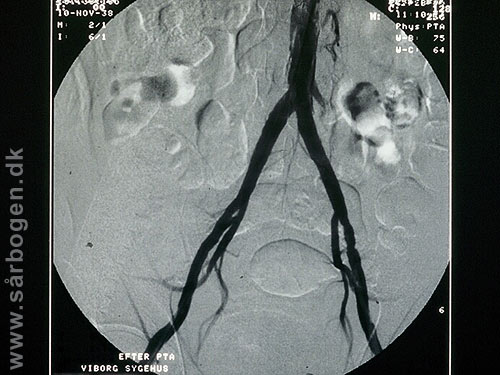

Før PTA af iliacakar...

Zoom

Under PTA af iliacak...

Efter PTA af iliacak...